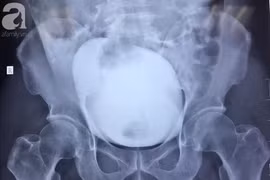

Sau một cú ngã tưởng chừng không quá nghiêm trọng, nam thanh niên 29 tuổi ở Sơn La phải nhập viện cấp cứu trong tình trạng vỡ bàng quang.

Nhịn tiểu khi uống bia, người đàn ông 46 tuổi bị vỡ bàng quang nguy hiểm, được các y bác sĩ Bệnh viện Nhân dân 115 cứu sống.